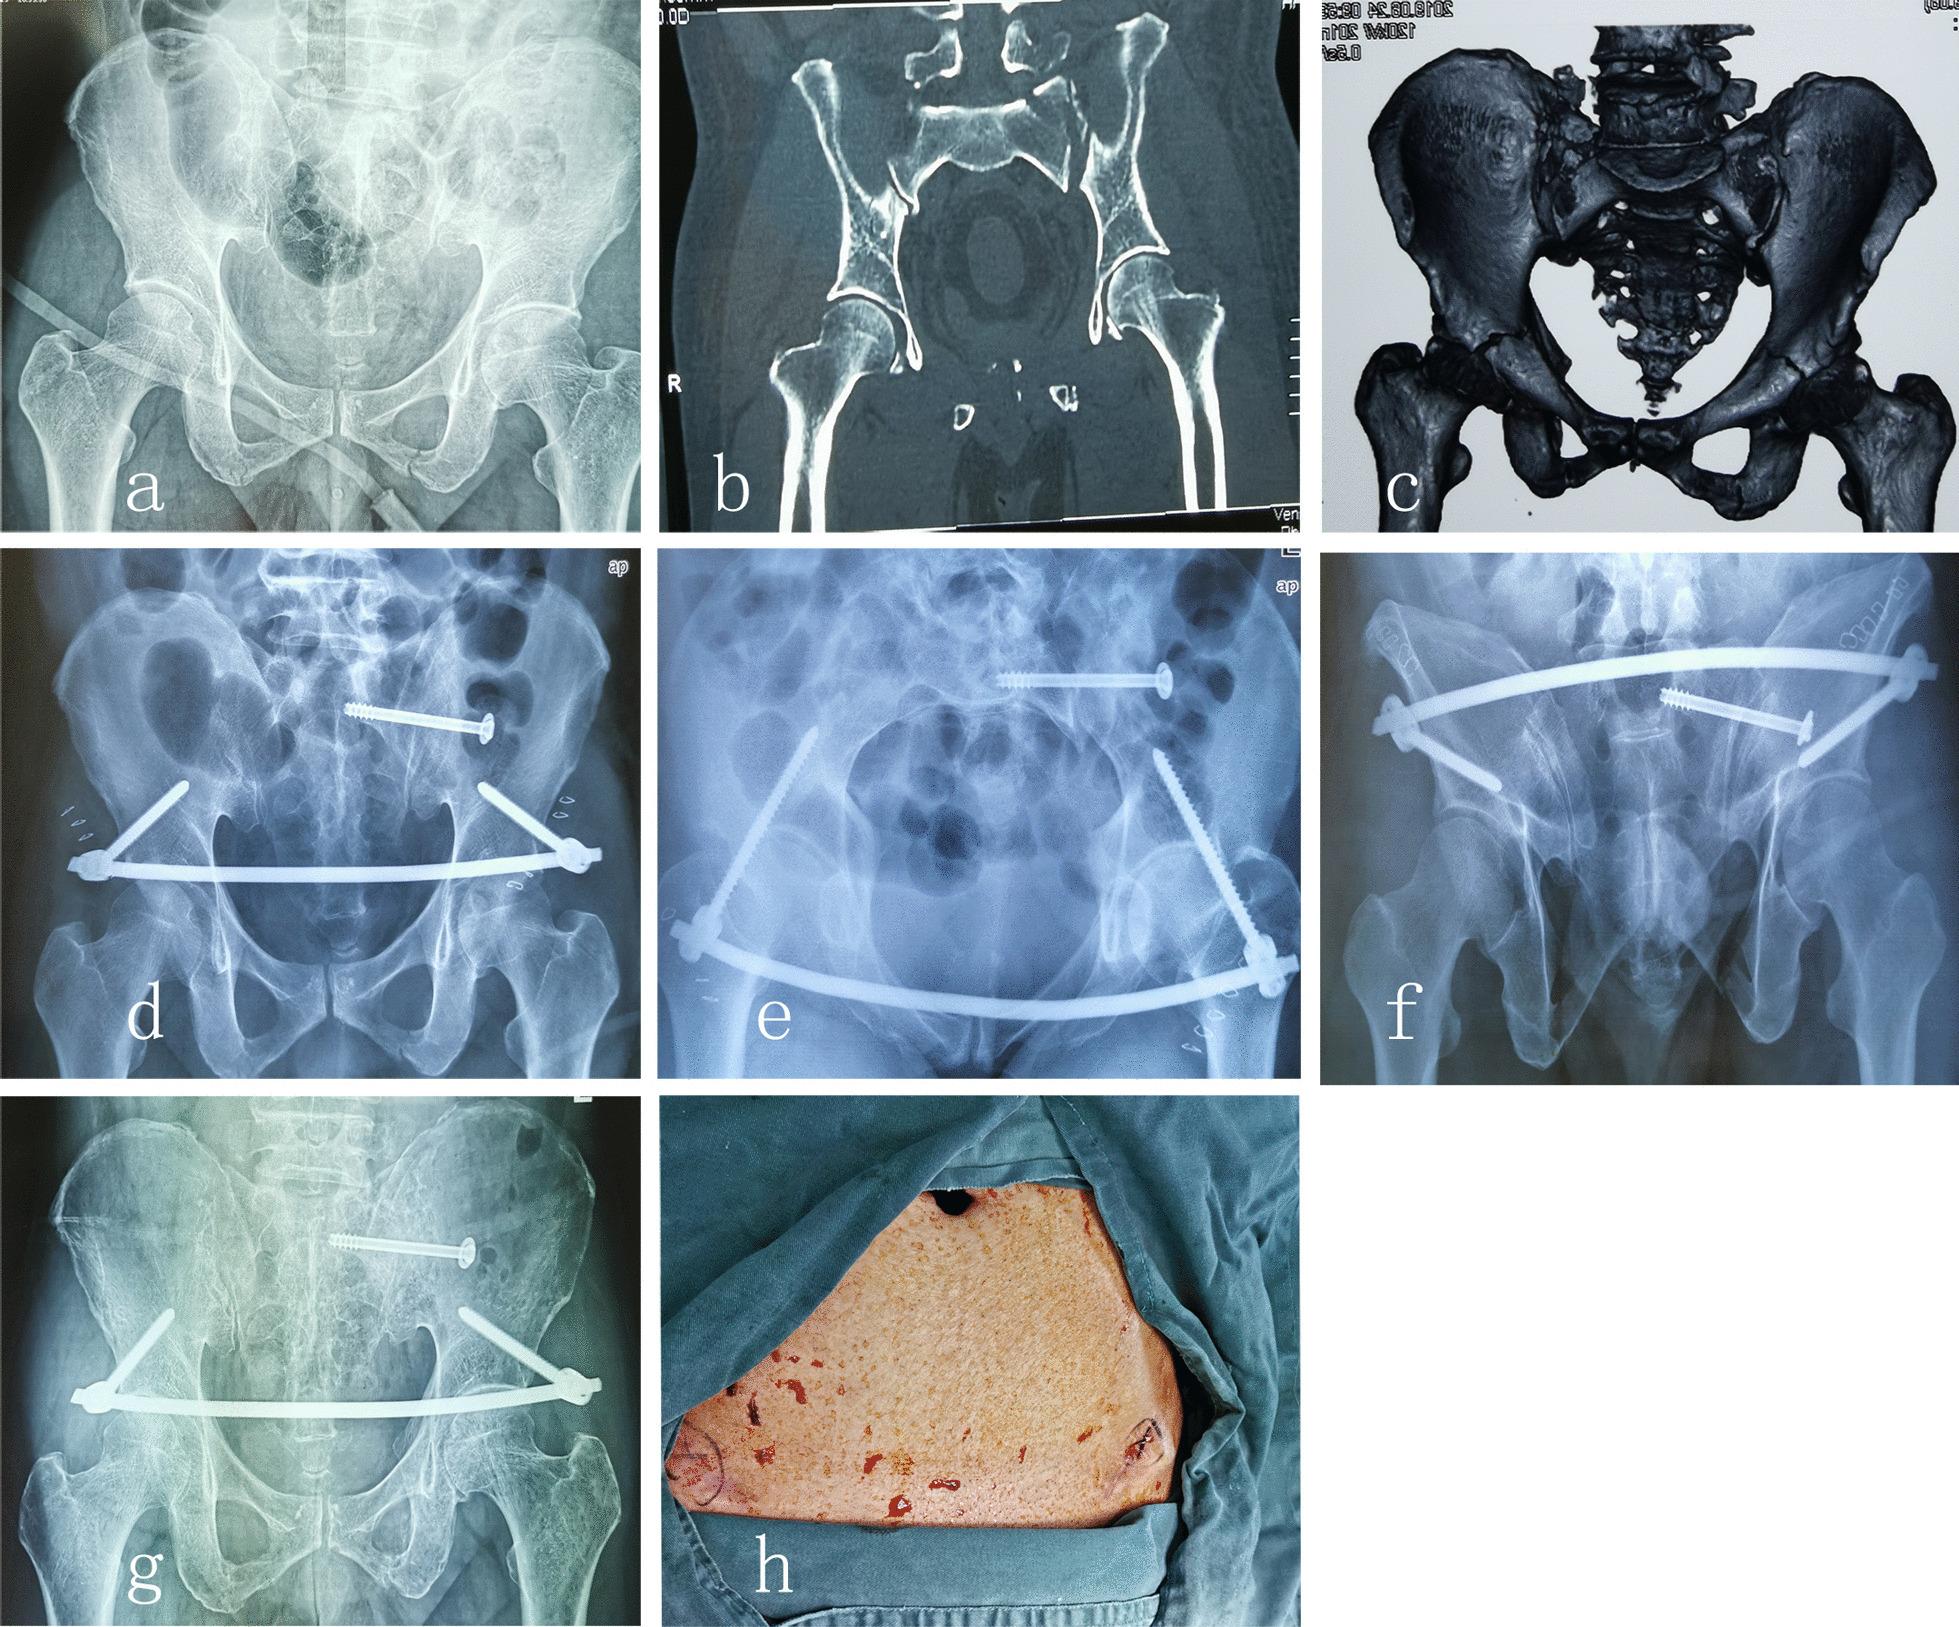

The aim of this study is to compare the clinical and biomechanical outcome of INFIX plus single with two sacroiliac screw fixation for unstable pelvic fractures of Type C.

Sixteen cadavers were randomly subjected to INFIX plus single or double sacroiliac screw fixations and then mounted onto the ElectroForce loading machine under different vertical loads. To investigate the clinical outcomes of the two techniques, nineteen patients were retrospectively analyzed. The main outcome measures were postoperative radiographic reduction grading (using the Tornetta and Matta grading system), functional outcome (using the Majeed scoring system), and incidence of complications.

In the biomechanical study, INFIX plus double sacroiliac screw fixation showed better biomechanical stability than fixation with a single sacroiliac screw (p < 0.05). In our clinical case series, all 19 patients had bony union 6 months after the operation. INFIX plus double sacroiliac screw fixation also demonstrated a better functional outcome and a higher radiographic satisfactory rate than INFIX plus single sacroiliac screw fixation (79.25 ± 5.47; 91.33 ± 4.97; p < 0.05), (77.78% vs. 60%; p = 0.05). One patient in INFIX plus single-screw fixation group had screw loosening at 6-month follow-up postoperatively. One case in each group suffered heterotopic ossification and the lateral femoral cutaneous nerve paralysis, and one patient suffered from infection.